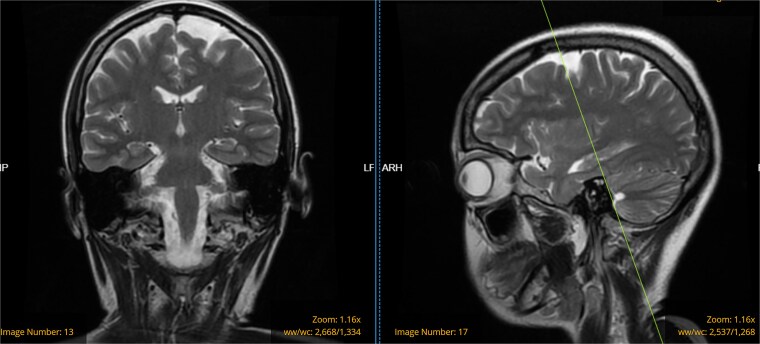

Sjögren综合征(SS)是一种自身免疫性疾病,导致外分泌腺和全身器官的慢性炎症和退行性改变,估计发病率为每10万人年6.92例。这个病例说明了一个不常见的相关性,在围生期患者出现新发癫痫发作,原发性Sjögren病(pSS),和慢性肾动脉狭窄。当pSS与其他无典型症状的全身性疾病同时出现时,可能未被发现。本文强调孕妇pSS的独特特征,提出在诊断为SS和入院期间新发癫痫之前发现的RAS可能预示着血管炎的后果。

Sjögren's syndrome (SS) is an autoimmune disorder that results in chronic inflammatory and degenerative alterations in the exocrine glands and systemic organs, with an estimated incidence rate of 6.92 per 100 000 person-years. This case illustrates an uncommon correlation in a patient who developed new-onset seizures during the peripartum period, primary Sjögren's disease (pSS), and chronic renal artery stenosis. pSS may go undetected when it manifests with other systemic disorders without classical symptoms. This paper emphasizes the distinct characteristics of pSS in pregnant women, proposing that the RAS, identified prior to the diagnosis of SS and new-onset seizure during this admission, may signify vasculitis consequence.